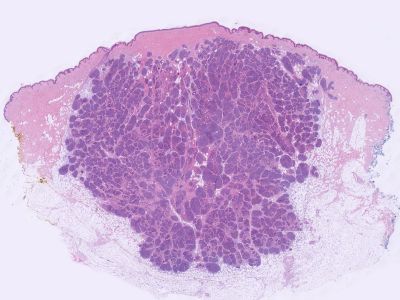

PA:De tumor ligt

los van de epidermis en is opgebouwd uit talloze polygonale nesten van

tumorcellen die als een puzzel in elkaar passen ('jigsawlike pattern').

Typisch is ook dat de velden omringd zijn door een dikke hyaliene membraan.

Deze membraan bestaat vooral uit type IV collageen. In de velden kunnen 2

celtypen worden onderscheiden: een rand van kleinere basofiele cellen en een

centrum van grote bleke cellen. Ook buisvormige structuren en lumina kunnen

worden gezien. In tegenstelling tot spiradenoma ontbreekt een lymfocytair

infiltraat. Wel worden dendritische cellen gezien, waarschijnlijk Langerhans

cellen (CD1a-positief). Immunohistochemische kleuringen tonen

myoepitheliale, apocriene, eccriene, ductale, and secretoire differentiatie

aan. Zie ook de

ingescande PA-coupe van de

afdeling pathologie van de University of

Toronto.

![Histologie cylindroma (click on photo to enlarge) [source: Kevin Kwee / Afdeling Pathologie MUMC] Histologie cylindroma](../../../pacoupes/thumbnails/cylindroom.jpg) |

![Histologie cylindroma (click on photo to enlarge) [source: Kevin Kwee / Afdeling Pathologie MUMC] Histologie cylindroma](../../../pacoupes/thumbnails/cylindroom-eccrien.jpg) |

| ingescande coupe (zoom) |

ingescande coupe (zoom) |